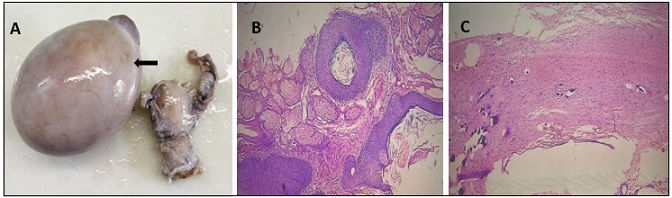

Synchronous multiple primary malignancies are rare clinical condition, and the occurrence of triple synchronous primary tumors are exceptionally uncommon. Among these, the simultaneous occurrence of primary gastric, renal, and ovarian tumor has seldom been reported in the literature. We present a case of a 70 year- female who presented with abdominal pain and endoscopic biopsy showed gastric adenocarcinoma. CECT abdomen and pelvis subsequently revealed an incidental right renal and ovarian tumor. The patient underwent curative surgical resection for all three tumors in a single operative session. Post-surgical histopathology confirmed Clear cell renal cell carcinoma and Ovarian mature cystic teratoma. There was no evidence of metastasis among the tumors. Elderly patient with gastric carcinoma have a higher risk of developing a synchronous tumor than younger people. This case highlights the importance of thorough diagnostic evaluation of multiple primary malignancies in an elderly patients with gastric cancer , as the differentiation between metastatsis and synchronous primaries significantly influences the planning of treatment. Early detection and multidisciplinary approach are essential for optimizing outcomes in such rare and complex presentations.